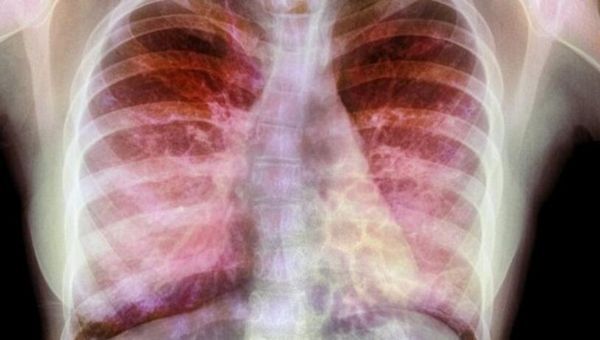

文章中,研究者解释了为何囊性纤维化患者非常容易患上呼吸道感染,25年前,研究人员就发现CFTR基因的突变会诱发肺部囊性纤维化,CFTR基因能表达产生CFTR蛋白帮助在细胞内外运输氯离子,如果没有这种离子运输的话,肺部中的粘液就会越来越粘厚,从而就很容易诱发肺部被细菌感染,尤其是假单胞菌,细菌的感染也会加速机体炎性反应的发生,从而导致持续性难以治疗感染性疾病的发生。

这项研究中,研究者发现,CFTR突变会通过一种完全不同的方式来促进感染进行;研究者Sebastian A. Riquelme博士表示,携带CFTR突变的细胞或许对细菌免疫反应较低,从而就会降低机体清除感染的能力,也会促进炎症扩张;这一点看起来非常有趣,因为其阐明了一种平行的解除管制的免疫学机制,这种机制会促进呼吸道破坏,这种效应远远超过了CFTR对粘液的效应。

当然了,这也是PTEN发挥作用的场所,研究人员并不清楚PTEN如何参与囊性纤维化的发病过程,如今通过对缺失PTEN的小鼠进行研究后研究人员发现小鼠对假单胞菌会产生严重的炎性反应,而且小鼠体内也会表现出像在囊性纤维化患者中出现的清除能力下降的表现。当PTEN位于肺部细胞和免疫细胞表面时,其能帮助有效清除假单胞菌,并且抑制炎症反应,但PTEN似乎只有在吸附到CFTR上才会表现出这样的作用。